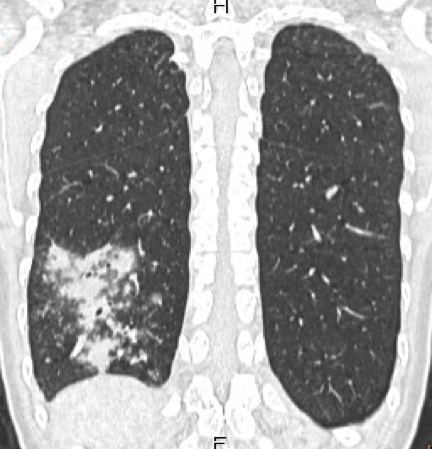

80列マルチスライス撮影により、撮影は約10秒程度です。また、被ばくに対し配慮した設計により、高感度のX線検出器を使用し、低線量、高画質の撮影で安心して検査を受けて頂く事が出来ます。